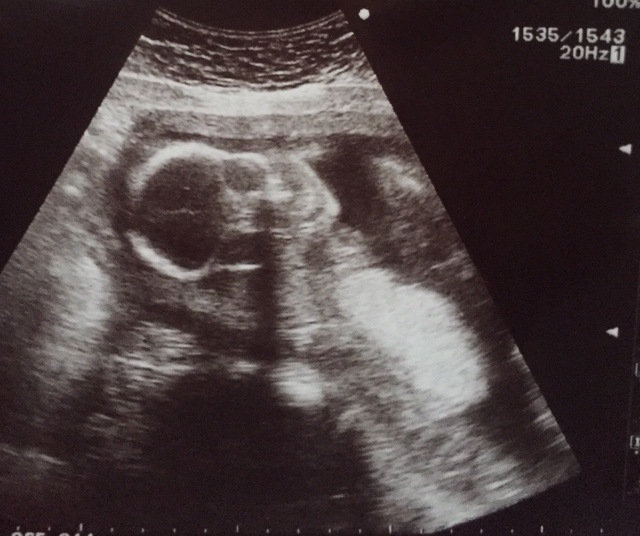

22週0日(22w0d・女の子)|ao:-) さん(29歳)

エコー写真撮影時のエピソード:

なかなか性別が分からない我が子。

この日もお股を見せてくれず。

すこーし、週数より小さめに育っている我が子ですが、私自身も小さめに生まれたのでそんなに不安は感じませんでした。

つわりも少なく、安定期に入って主人と一泊旅行に行ってきた次の日の健診だったので体重増加を先生に注意されたのは今となっては良い思い出です。